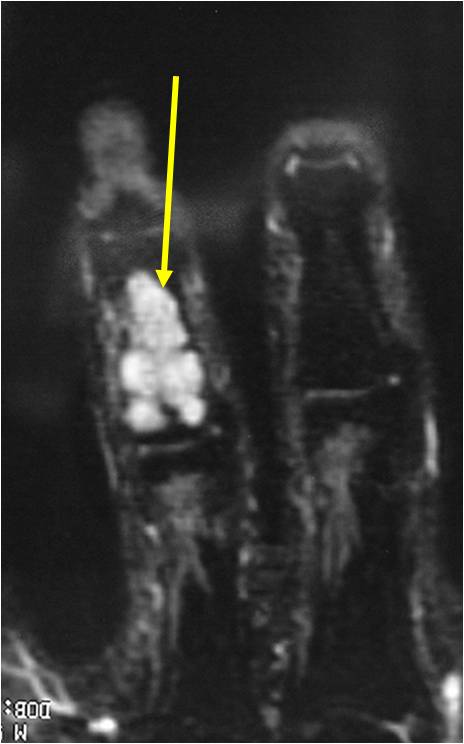

- T2 Weighted Images: High Signal Intensity

- High water content shows as high signal on T2 weighted images

- Calcifications will be low signal

- Marked increased intensity long TR images

T2: High Signal No Soft Tissue Component